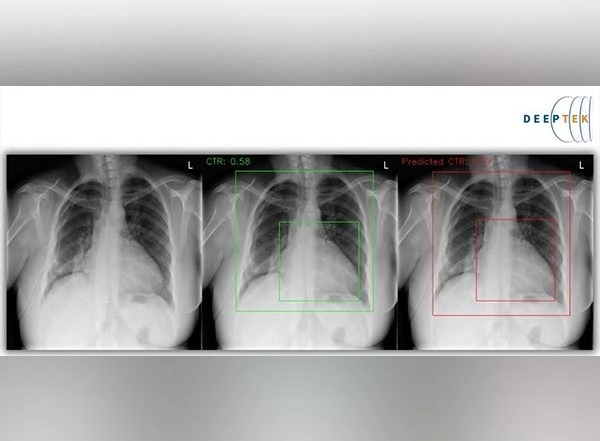

Enlarged heart as seen on chest radiographs can be quite subjective. The AI tool helps in objective assessment of the findings and it also quantifies the same and provides tools for easier analysis and faster reporting. The automated approach used to measure cardiothoracic ratio (CTR) makes reporting objective, structured and faster.

Dr Amit Kharat, Radiologist and Co-founder at DeepTek stated, "To address the two stages of the cardiomegaly detection challenge, we constructed different neural network models. The first model discriminated between X-rays taken from the AP and PA perspectives. To calculate the CTR, the second model used the heart and thoracic diameters from the PA X-rays." Similarly for pleural fluid and pulmonary edema we trained the AI model on a substantially large set of annotated X-rays."